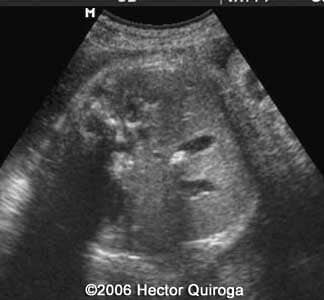

Gallstones Hector Quiroga, MD Article Published: May 2, 2006 Barquisimeto, Venezuela These are some imagesĀ of a fetus with a few gallstones diagnosed at 32 weeks. Discussion Board Start a discussion about this article Add to Favorites Favorite